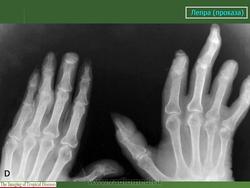

Что касается нервной формы проказы (рис. 216), то наиболее ранним, постоянным и общим рентгенологическим ее проявлением служит остеопороз. IK остеопорозу рано присоединяются явления остеолиза. Иконография (т. е. описание картины) остеолиза дается различными авторами в традиционном для лепрологии стиле в чрезвычайно тонких и кропотливых внешне описательных образах. Здесь преобладают сравнения с общеизвестными предметами, как, например, отточенными кончиками карандаша, шахматными пешками и другими фигурами, кнопками, пуговицами для воротника, запонками, тающими свечами, обсосанными леденцами, столбиками, иглами и т. д. Существенно то, что налицо частичное или полное рассасывание и исчезновение костных элементов без их замещения другой тканью и без продуктивной репаративной реакции. Характерно истончение и укорочение костей, в первую очередь ногтевых фаланг. Рассасывание ногтевой фаланги начинается с ее ногтевого отростка. Структура бугорка становится крупнопористой, ноздреватой. Затем срезается дистальный или боковой край, развивается плоская или вогнутая узура, постепенно увеличивающаяся, а затем и весь ногтевой отросток сходит на нет; обнажается шейка. Основание фаланги рассасывается с одного края или с обеих сторон, иногда и целиком. В дальнейшем без каких-нибудь клинических признаков очередь доходит до фаланг средних и основных, а также пястных и плюсневых костей, с переходом на запястье и предплюсну, порой до полного исчезновения скелета одного, нескольких, многих или всех пальцев.

В локализации этих костных поражений трудно определить какую-нибудь иннервационную закономерность, т. е. связь с тем или иным иннервационным районом, что свойственно всем костным поражениям "а нервнотрофической почве. Если в одних случаях имеется симметричность поражений, то в подавляющем большинстве случаев удивляет именно асимметрия двусторонних поражений. Тяжесть калечения при нервной проказе не находится в прямой связи с длительностью забдлевания.